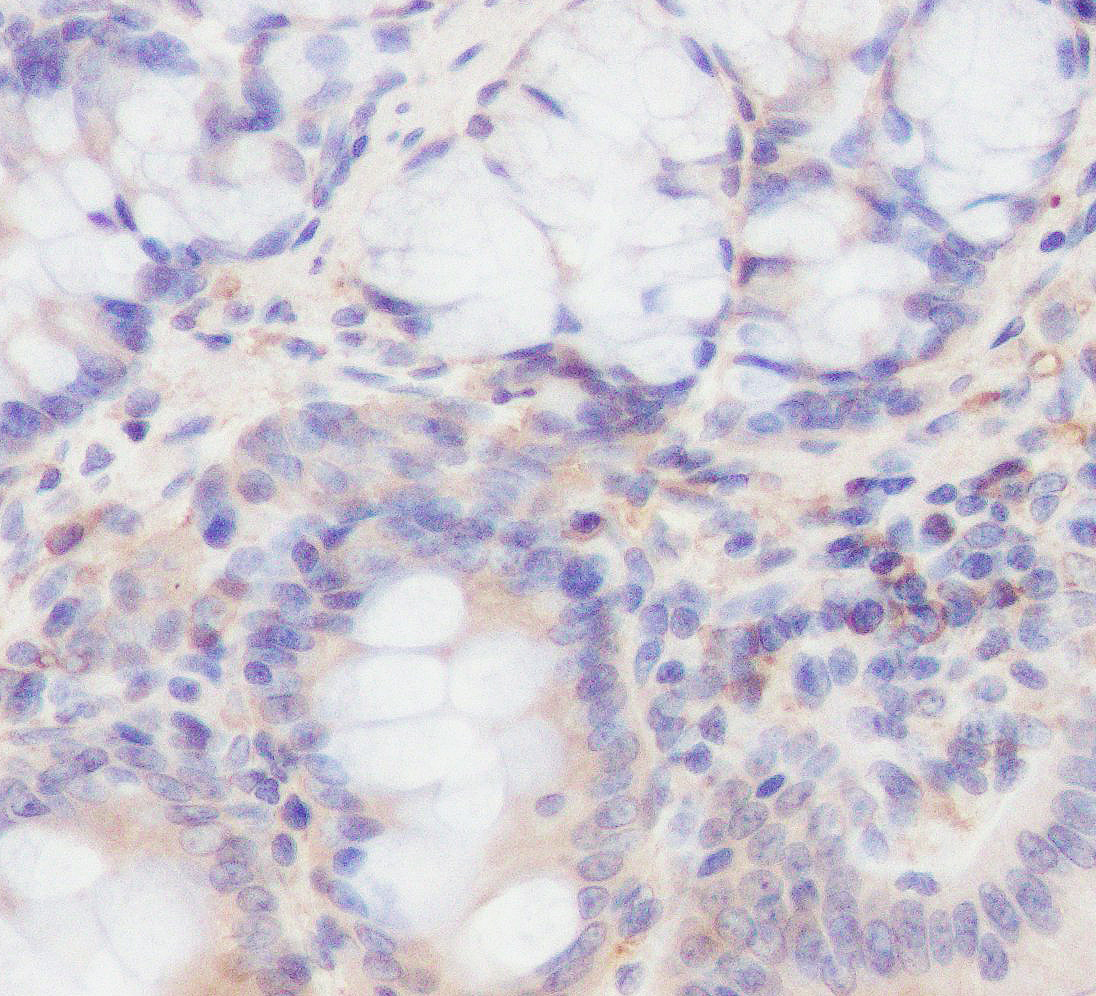

Formalin-fixed, paraffin-embedded human colon carcinom tissue stained for Phospho-PI3 Kinase p85α(Tyr607) using 12057 at 1/100 dilution in immunohistochemical analysis.